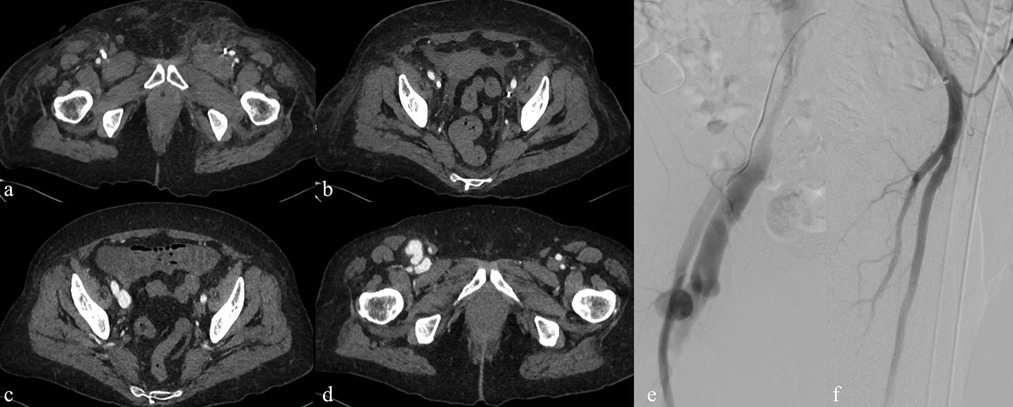

Background: Tunneled cuffed catheter (TCC) remains a crucial vascular access option for patients undergoing hemodialysis, particularly in those who are not candidates for arteriovenous fistulas or grafts. However, placement carries immediate and delayed complications. Objective: This narrative review aims to provide a comprehensive overview of the complications encountered during and after the placement of a TCC for hemodialysis, highlighting current evidence, risk factors, prevention strategies, and management approaches. Methods: A critical selection of relevant literature was performed through PubMed and Scopus databases, focusing on articles published in the last two decades. Particular attention was given to studies reporting on mechanical, infectious, thrombotic, and late-onset complications, as well as technical factors influencing outcomes. Results: Complications of TCCs can be classified as immediate (e.g., arterial puncture, pneumothorax, bleeding), early (e.g., catheter malposition, exit-site infections), and late (e.g., central venous stenosis, catheter-related bloodstream infections, thrombosis). Patient-and procedure-related factors increase risk. Ultrasound and fluoroscopy, strict sterility, and timely management reduce complications rates. Conclusion: TCCs are indispensable in selected patients, but understanding their complications is key to patient safety and outcomes. Optimal outcomes depend on accurate patient selection, operator expertise, and standardized post-placement care.